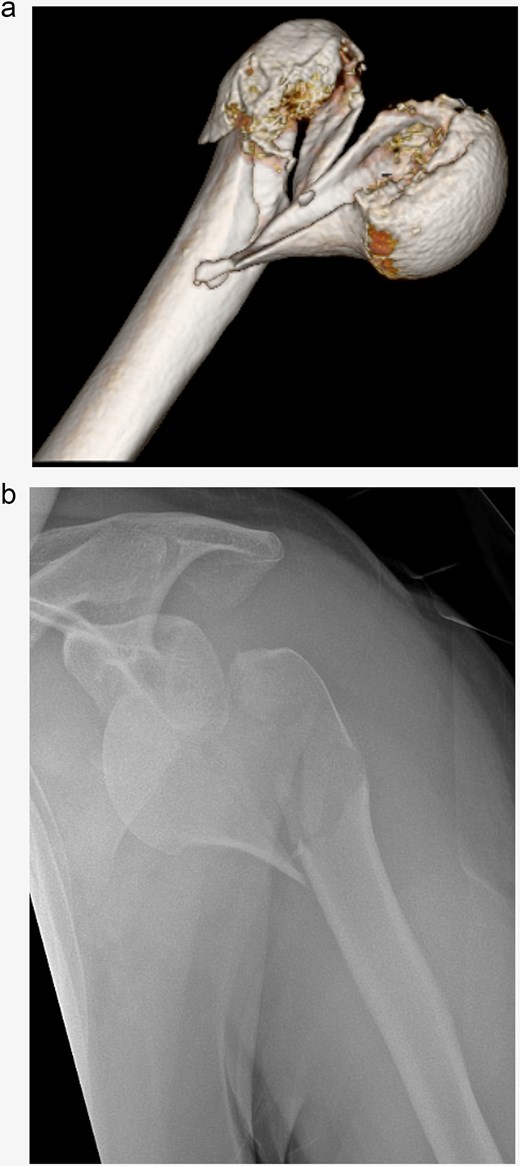

In subsequent clinical and radiological follow-ups at 2, 6, and 24 weeks postoperative, the humeral head depression showed regression, and the patient was able to progressively increase joint demands (Fig. 3). Training under physiotherapeutic supervision was difficult because of his secondary diagnoses. In the end after 6 Months he was unaffected in his daily living and painless.